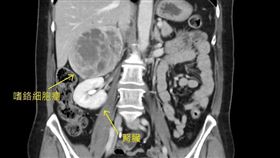

他嚴重心悸檢查竟心房顫動 醫:中風高5倍

53歲陳先生2年多前感到心臟不適且心悸嚴重,就醫檢查...